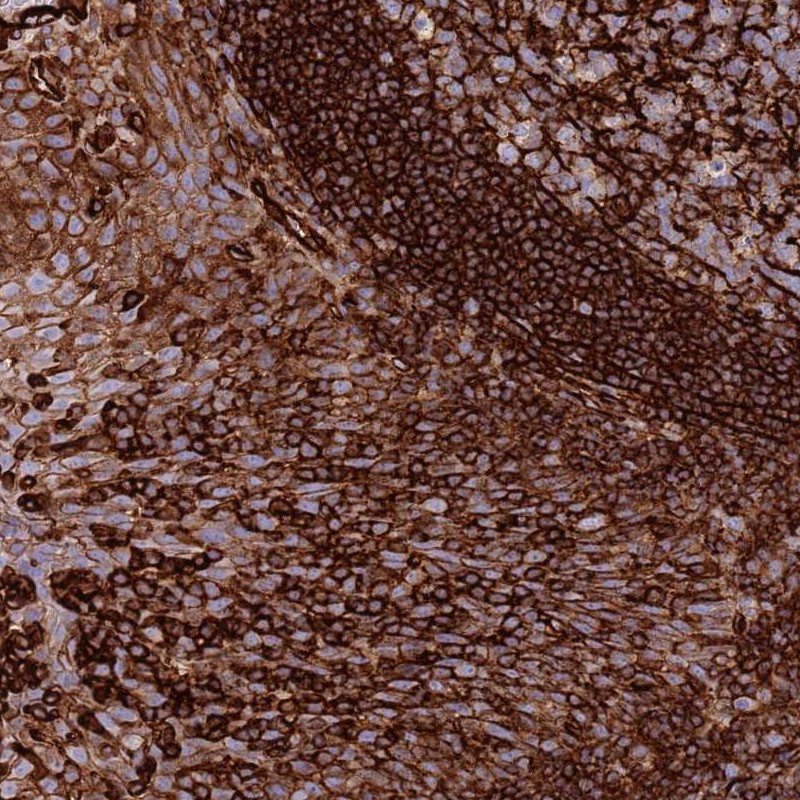

Immunohistochemical staining of human tonsil shows strong membranous and cytoplasmic positivity in squamous epithelial cells along with strong positivity in germinal center cells and non-germinal center cells.